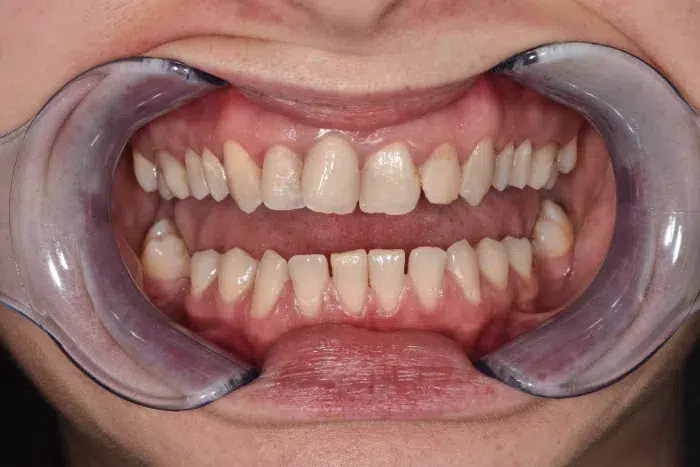

Caz de reabilitare totală orală.

Provocarea acestui caz a fost in reabilitarea totală a pacientului atâta a maxilarului superior cat și a mandibulei, tratând absolut toți dinții prezenți și reconstruindu-i cu pivoți de fibră de sticlă pentru a putea obține o susținere suficientă pentru viitoarele coroane.

Grupul superior fiind distrus complet, am efectuat tratamente la microscop, reconstrucția individuală a fiecărui dinte, tratamente parodontale cu laser pentru sănătatea ginigivala și am optat pentru coroane individuale de zirconiu ceramică pentru un plus de duritate și protecție a dinților cat și pentru o estetică frumoasă. Au fost folosite un set de provizorii de lungă durată pentru reechilibrarea articulației și muscaturii.

Pacientul a beneficiat inferior de igienizare în profunzime , detartraj și airflow, tratamente endodontice , obturații ( plombe) , tratamente parodontale cu laser iar în final punți și coroane individuale de zirconiu ceramica.

Termen de finalizare 2 săptămîni de la amprentarea finală.